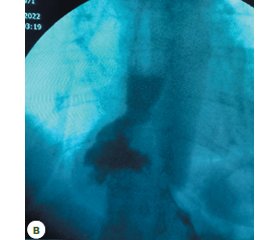

Мета дослідження: порівняти ефективність та безпеку відомих лапароскопічних антирефлюксних втручань при лікуванні грижі стравохідного отвору діафрагми (ГСОД) та встановити причини їх невдач при ретроспективному дослідженні. Матеріали та методи. У ретроспективному порівняльному дослідженні проаналізовані віддалені результати основних способів лапароскопічної пластики ГСОД різних типів та ступенів. Пацієнти, яким виконано фундоплікацію за Nissen, увійшли до групи 1 — це 74 особи (56,5 %). До групи 2 увійшли 37 (28,2 %) пацієнтів, яким виконано фундоплікацію за Toupet, а до групи 3 увійшли 20 (15,3 %) пацієнтів, яким виконано фундоплікацію за Dor. Дослідження включає пацієнтів, прооперованих у клініці інституту за 7-річний період, з можливістю клінічної оцінки віддалених результатів і виключенням факторів, що впливають на результати пластики. Усім пацієнтам проводили рентгенологічне та ендоскопічне дослідження стравоходу, шлунка, дванадцятипалої кишки, манометрію. Результати. При аналізі скарг обстежених хворих 1, 2, 3 груп у післяопераційному періоді можна зазначити, що найбільш статистично вагомими показниками були дисфагія, регургітація, кашель, печія, здуття живота, тяжкість у животі після їжі, біль за грудиною, (p < 0,05, точний критерій F). Під час ендоскопічного дослідження рефлюкс-езофагіт був виявлений у 16 (21,6 %) пацієнтів 1 групи, у 7 (18,9 %) пацієнтів 2 групи та у 2 (10,0 %) пацієнтів 3 групи. Ерозії нижньої третини стравоходу виявлено у 14 (18,9 %) пацієнтів 1 групи, у 6 (16,2 %) пацієнтів 2 групи та у 2 (10,0 %) пацієнтів 3 групи. В 1 (1,4 %) пацієнта 1 групи в післяопераційному періоді під час ендоскопічного дослідження було виявлено стриктуру стравоходу. Ознаки наявності «другого входу» в шлунок виявлено у 16 (13,5 %) пацієнтів 1 групи, у 5 (13,5 %) пацієнтів 2 групи та у 2 (10,0 %) пацієнтів 3 групи. В 1 (1,3 %) пацієнта 1 групи відмічено дислокацію фундоплікаційної манжетки, як наслідок — деформація стравохідно-шлункового переходу та больовий синдром. Спазм воротаря виявлено у 8 (8,8 %) пацієнтів 1 групи, у 3 (2,9 %) пацієнтів 2 групи та в 1 (5,0 %) пацієнта 3 групи. Під час рентгенологічного дослідження було виявлено рецидивну ГСОД: в 1 групі — у 10 (13,5 %), у 2 групі — у 5 (13,5 %) пацієнтів, у 3 групі — у 2 (10,0 %) пацієнтів. При оцінці якості життя (ЯЖ) пацієнтів після оперативних втручань виявлено, що у 1 групі середній бал ЯЖ за опитувальником GERD-HRQL становив (11,0 ± 5,5 (3–35)) бала, у 2 групі — (19,0 ± 8,0 (3–35)) бала, у 3 групі — (16,0 ± 7,3 (3–35)) бала, тобто був досить високим у всіх групах. Розподіл за задоволеністю станом у 1 групі був таким: задоволені — 34 пацієнти (45,9 %), частково задоволені — 24 пацієнти (32,4 %), незадоволені — 16 пацієнтів (21,6 %). Розподіл за задоволеністю станом у 2 групі був таким: задоволені — 16 пацієнтів (43,2 %), частково задоволені — 14 пацієнтів (37,8 %), незадоволені — 7 пацієнтів (19,0 %). Розподіл за задоволеністю станом у 3 групі був таким: задоволені — 9 пацієнтів (45,0 %), частково задоволені — 8 пацієнтів (40,0 %), незадоволені — 3 пацієнти (15,0 %). У віддаленому післяопераційному періоді ускладнення мали місце у 40 (54,1 %) пацієнтів 1 групи (пілороспазм, дисфагія, диспептичні розлади, рефлюкс-езофагіт, стриктури стравоходу), у 14 (37,8 %) пацієнтів 2 групи та у 6 (30,0 %) пацієнтів 3 групи. Вірогідних відмінностей за частотою післяопераційних ускладнень між групами не було (54,1 проти 37,8 %, p > 0,05, точний критерій F; 54,1 проти 30,0 %, p > 0,05, точний критерій F; 37,8 проти 30,0 %, p > 0,05, точний критерій F). Висновки. 1. Частка пацієнтів, які незадоволені результатами оперативного втручання за даними GERD-HRQL, після фундоплікації за Nissen становила 21,6 % (11,0 ± 5,5 бала), після фундоплікації за Toupet — 19,0 % (19,0 ± 8,0 бала), після фундоплікації за Dor — 15,0 % (16,0 ± 7,3 бала). 2. Невдачі відомих способів антирефлюксних лапароскопічних втручань при ГСОД пов’язані з руйнуванням складових фізіологічної кардії і мали місце у 40 (54,1 %) пацієнтів 1 групи (пілороспазм, дисфагія, диспептичні розлади, рефлюкс-езофагіт, стриктури стравоходу), у 14 (37,8 %) пацієнтів 2 групи та у 6 (30,0 %) пацієнтів 3 групи. 3. Фундоплікація за Nissen в післяопераційному періоді значно частіше супроводжувалася дисфагією та пілороспазмом порівняно з фундоплікаціями за Toupet та Dor (p < 0,05).

Background. The objective: to compare the effectiveness and safety of known laparoscopic antireflux interventions in the treatment of hiatal hernia and to detect the causes for their failure in a retrospective study. Materials and methods. In a retrospective comparative study, the long-term results of using the main methods of laparoscopic plastic surgery for hiatal hernias of various types and degrees were analyzed. Seventy-four (56.5 %) patients who underwent Nissen fundoplication were included in group 1. Group 2 consisted of 37 (28.2 %) people who underwent Toupet fundoplication and group 3 included 20 (15.3 %) patients who underwent Dor fundoplication. The study includes patients operated in the clinic of the institute over a 7-year period, with the possibility of clinical evaluation of long-term results and the exclusion of factors affecting the results of plastic surgery. All patients underwent X-ray and endoscopic examinations of the esophagus, stomach, duodenum, as well as manometry. Results. When analyzing the complaints of patients from groups 1–3 in the postoperative period, it can be noted that the most statistically significant indicators were dysphagia, regurgitation, cough, heartburn, bloating, stomach heaviness, pain behind the sternum (p < 0.05, exact F test). During endoscopic examination, reflux esophagitis was detected in 16 (21.6 %) patients of group 1, in 7 (18.9 %) of group 2, and in 2 (10.0 %) patients of group 3. Erosions of the lower third of the esophagus were found in 14 (18.9 %) patients from group 1, in 6 (16.2 %) from group 2, and in 2 (10.0 %) patients from group 3. Esophageal stricture was detected in 1 (1.4 %) patient from group 1 in the postoperative period during endoscopic examination. Signs of a “second entrance” to the stomach were found in 16 (13.5 %) patients of group 1, in 5 (13.5 %) of group 2, and in 2 (10.0 %) of group 3. Dislocation of the fundoplication cuff was noted in 1 (1.3 %) patient of group 1, resulting in deformation of the esophagogastric junction and pain syndrome. Pylorospasm was found in 8 (8.8 %) patients from group 1, in 3 (2.9 %) from group 2 and in 1 (5.0 %) patient from group 3. During the X-ray examination, recurrent hiatal hernia was detected: in group 1 — in 10 (13.5 %) cases, in group 2 — in 5 (13.5 %), in group 3 — in 2 (10.0 %). When assessing the quality of life of patients after surgical interventions, it was found that in group 1, the average score on the Gastroesophageal Reflux Disease — Health-Related Quality of Life (GERD-HRQL) questionnaire was (11.0 ± 5.5 (3–35) points, in group 2 — (19.0 ± 8.0 (3–35)), in group 3 — (16.0 ± 7.3 (3–35)) points, which was quite high in all groups. The distribution of satisfaction with the condition in group 1 was as follows: satisfied — 34 (45.9 %) patients, partially satisfied — 24 (32.4 %), unsatisfied — 16 (21.6 %). The distribution of satisfaction with the condition in group 2 was as follows: satisfied — 16 (43.2 %) patients, partially satisfied — 14 (37.8 %), unsatisfied — 7 (19.0 %). The distribution of satisfaction with the condition in group 3 was as follows: satisfied — 9 (45.0 %) patients, partially satisfied — 8 (40.0 %), unsatisfied — 3 (15.0 %). In the distant postoperative period, complications (pylorospasm, dysphagia, dyspeptic disorders, reflux esophagitis, esophageal strictures) occurred in 40 (54.1 %) patients of group 1, in 14 (37.8 %) of group 2, and in 6 (30.0 %) of group 3. There were no significant differences in the frequency of postoperative complications between groups (54.1 vs. 37.8 %, p > 0.05, exact F test; 54.1 vs. 30.0 %, p > 0.05, exact F test; 37.8 vs. 30.0 %, p > 0.05, exact F test). Conclusions. 1. The number of patients who are unsatisfied with the results of surgery according to GERD-HRQL questionnaire, was 21.6 % ((11.0 ± 5.5) points) after Nissen fundoplication, 19.0 % ((19.0 ± 8.0) points) after Toupet fundoplication, and 15.0 % ((16.0 ± 7.3) points) after Dor fundoplication. 2. Failures of the known methods of antireflux laparoscopic interventions for hiatal hernia are associated with the destruction of the components of the physiological cardia and occurred in 40 (54.1 %) patients of group 1 (pylorospasm, dysphagia, dyspeptic disorders, reflux esophagitis, esophageal strictures), in 14 (37.8 %) in group 2 and in 6 (30.0 %) in the third group. 3. Nissen fundoplication in the postoperative period was significantly more often accompanied by dysphagia and pylorospasm compared to Toupet and Dor fundoplications (p < 0.05).